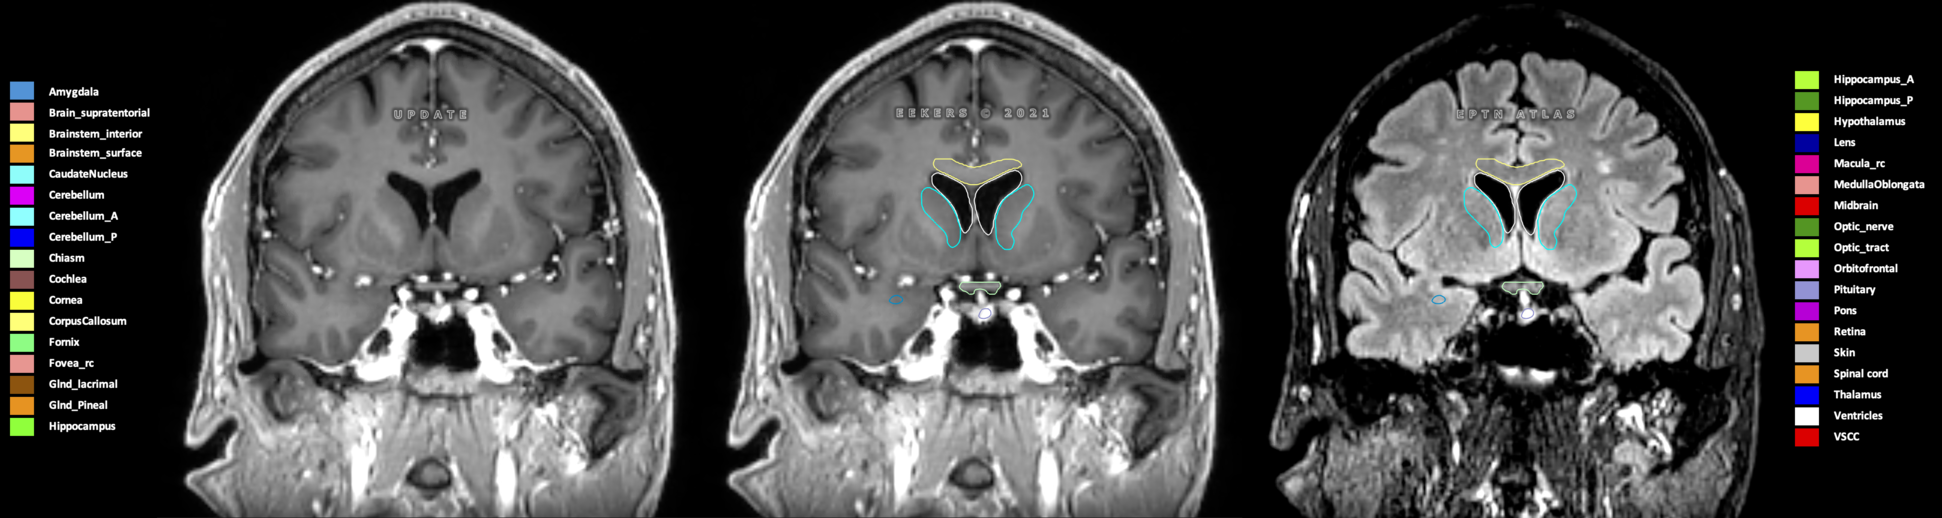

Eekers et al. have published an international neurological atlas for contouring of organs at risk in consensus with the European Particle Therapy Network (EPTN) in 2018 and an update in 2021. The purpose of this consensus atlas is to decrease inter- and intra-observer variability in delineating OARs relevant for neuro-oncology.

Included are all OARs known to be relevant for radiation-induced toxicity in neuro-oncology: brain, brainstem (midbrain, pons, medulla oblongata), chiasm, cerebellum (anterior & posterior), cochlea, cornea, hippocampus (anterior & posterior), hypothalamus, lens, lacrimal gland, optic nerve, pituitary, skin, and vestibular & semicircular canals. To further facilitate research on cognition, vision and radiological changes after irradiation of the brain, potential clinically-relevant OARs are included: amygdala, caudate nucleus, cerebellum (anterior & posterior), corpus callosum, fornix, macula, optic tract, orbitofrontal cortex, periventricular space (PVS), pineal gland, and thalamus.

Three-dimensional delineation of the 25 consensus OARs for neuro-oncology are shown on CT (WW/WL 120/40, 3000/600), 3T MR images, (T1Gd, T2FLAIR 1mm) and 7T MR (MP2RAGE 0.7 mm). All are presented in transversal, sagittal and coronal view.